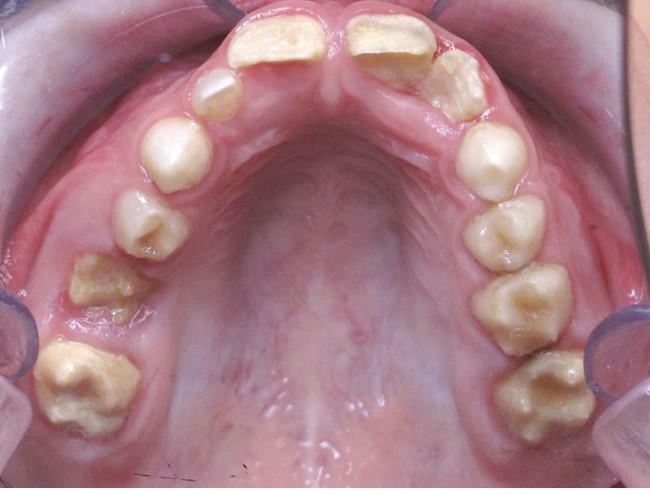

Il existe des anomalies dentaires (tabl. I) [1-12], mais aussi occlusales associées aux AI (fig. 1 et 2).

Selon de nombreuses études, l’anomalie occlusale la plus fréquemment retrouvée en association avec les AI est l’infraclusion antérieure, puisqu’elle est retrouvée chez 22 à 64 % des patients présentant cette affection, et encore plus chez les femmes [2,8,13-19]. Cette anomalie touche tous les types d’AI mais à des degrés très divers. Son incidence semble élevée dans les formes hypominéralisées, moindre dans les formes hypoplasiques et nettement moindre dans les formes hypomatures [8,17,18]. La sévérité de l’atteinte amélaire ne semble pas corrélée avec la présence ou l’intensité de cette malocclusion [17].